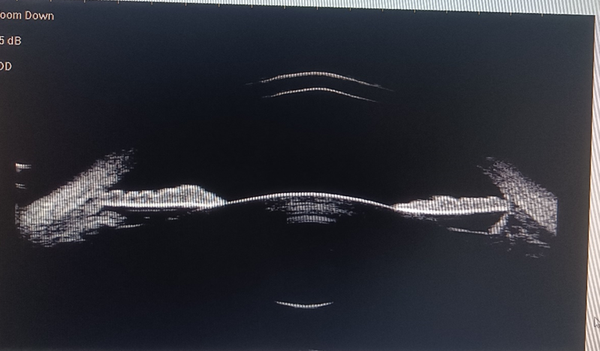

▲ 晶状体膨胀后前房形态

▲ 正常前房形态